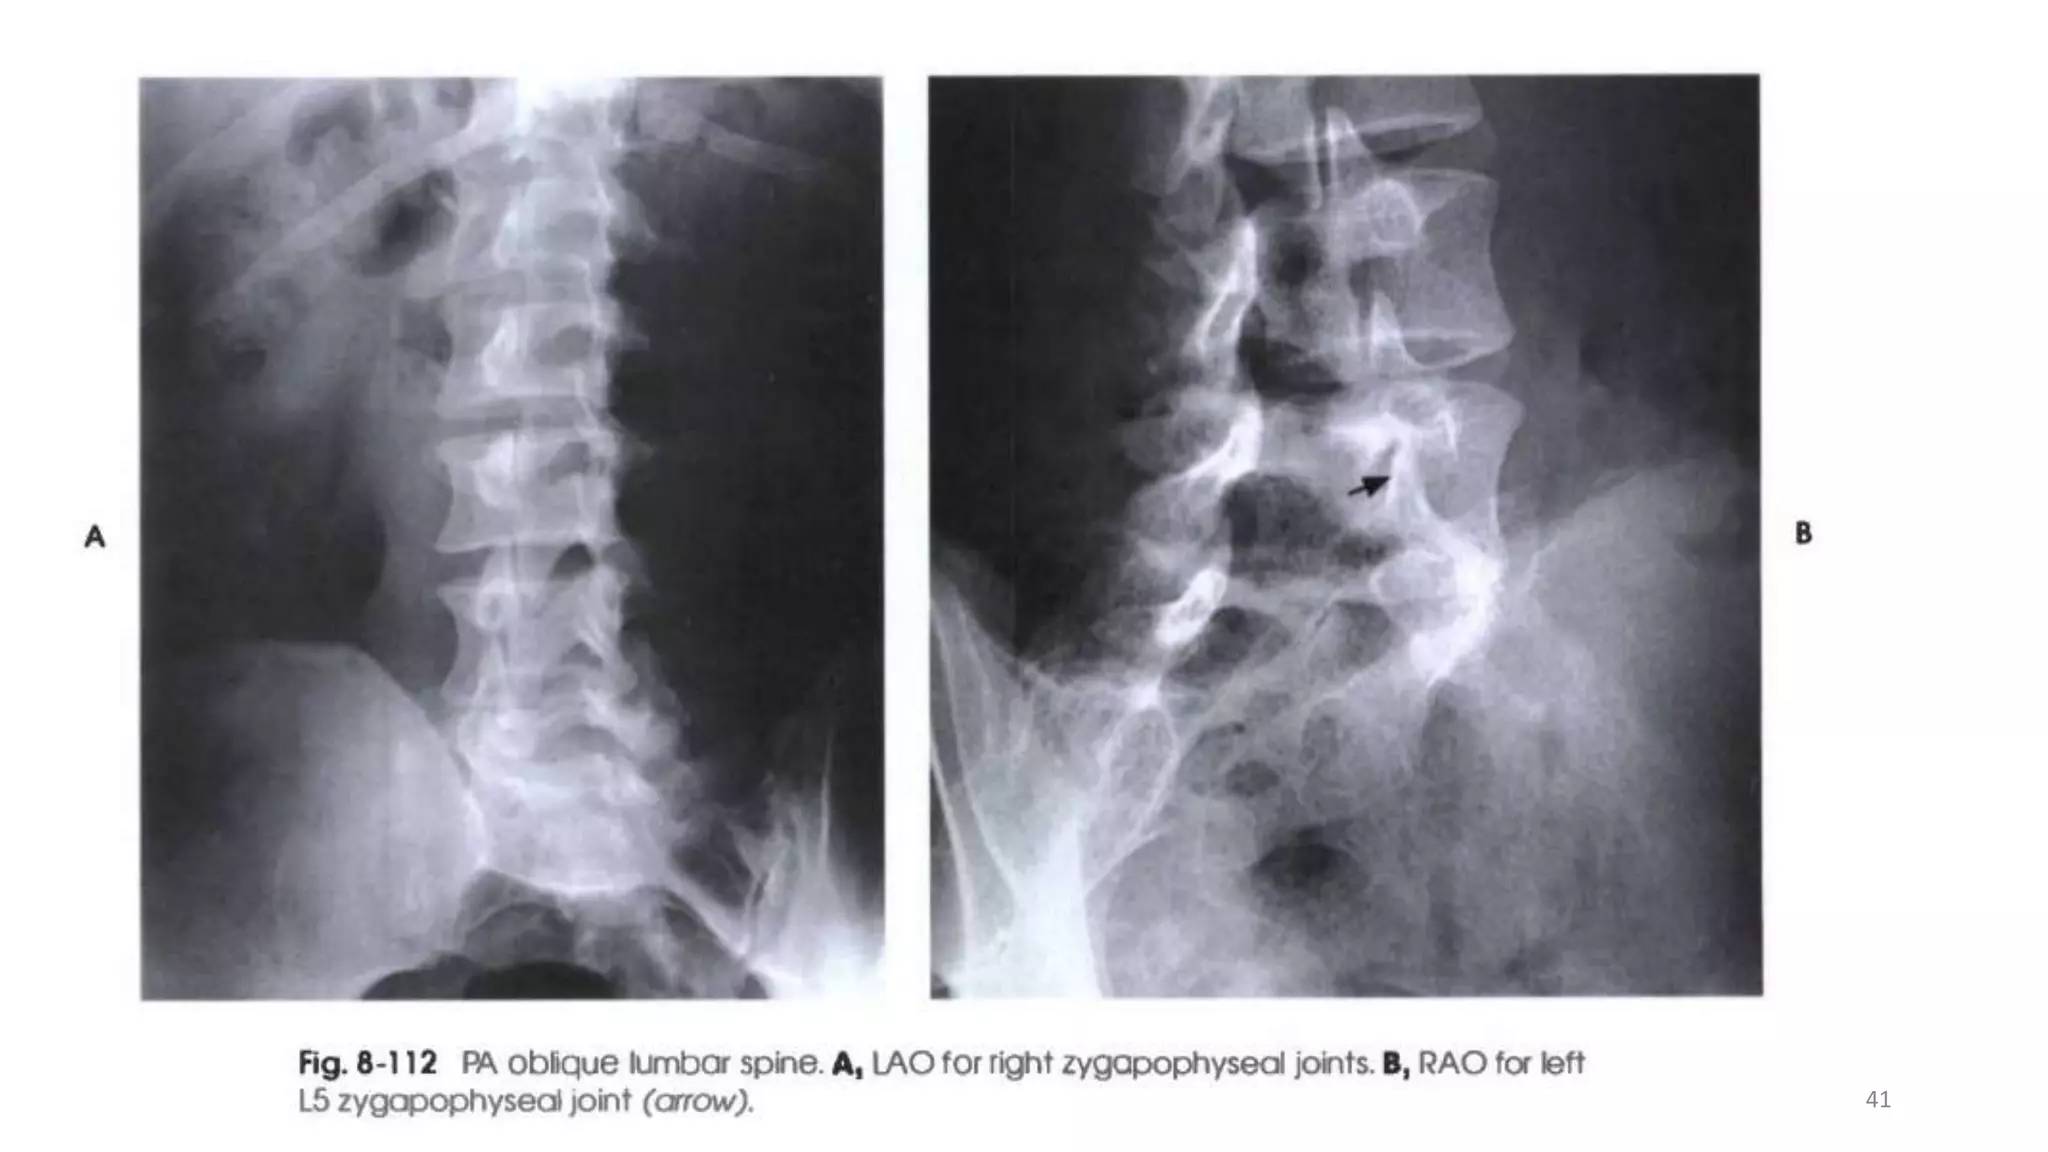

PA Oblique Projection RAO and LAO positions

• Examine the patient in the upright or recumbent prone position. The

recumbent position generally used because it facilitates immobilization.

• However, the OID is increased, which can affect resolution.

• The joints farthest from the IR are demonstrated with the PA oblique

projection (opposite the thoracic zygapophyseal joints).

• From the prone position, have the patient turn to a semi-prone position

and support the body on the forearm and flexed knee.

• Center the IR at the level of L3.

• To demonstrate the lumbosacral joint, position the patient as described

above but center L5.

Structures shown

• The resulting image shows an oblique projection of the lumbar or

lumbosacral vertebrae, demonstrating the articular processes of the

side farther from the IR .

• The fifth lumbosacral joint is usually well demonstrated in oblique

position.

• When the body is placed in a 30- to 50degree oblique position and

the lumbar spine is radiographed, the articular processes and

zygapophyseal joints are demonstrated .

• When the patient has been properly positioned, image of the

lumbar vertebrae have the appearance of "Scottie dog .”

40

Evaluation Criteria

• Area from the lower thoracic

vertebrae to the sacrum.

• Zygapophyseal joints farthest from

the IR.

• When the joint is not well

demonstrated and the pedicle is quite

anterior on the vertebral body, the

patient is not rotated enough.

posterior on the vertebral body, the

patient is rotated too much. 42